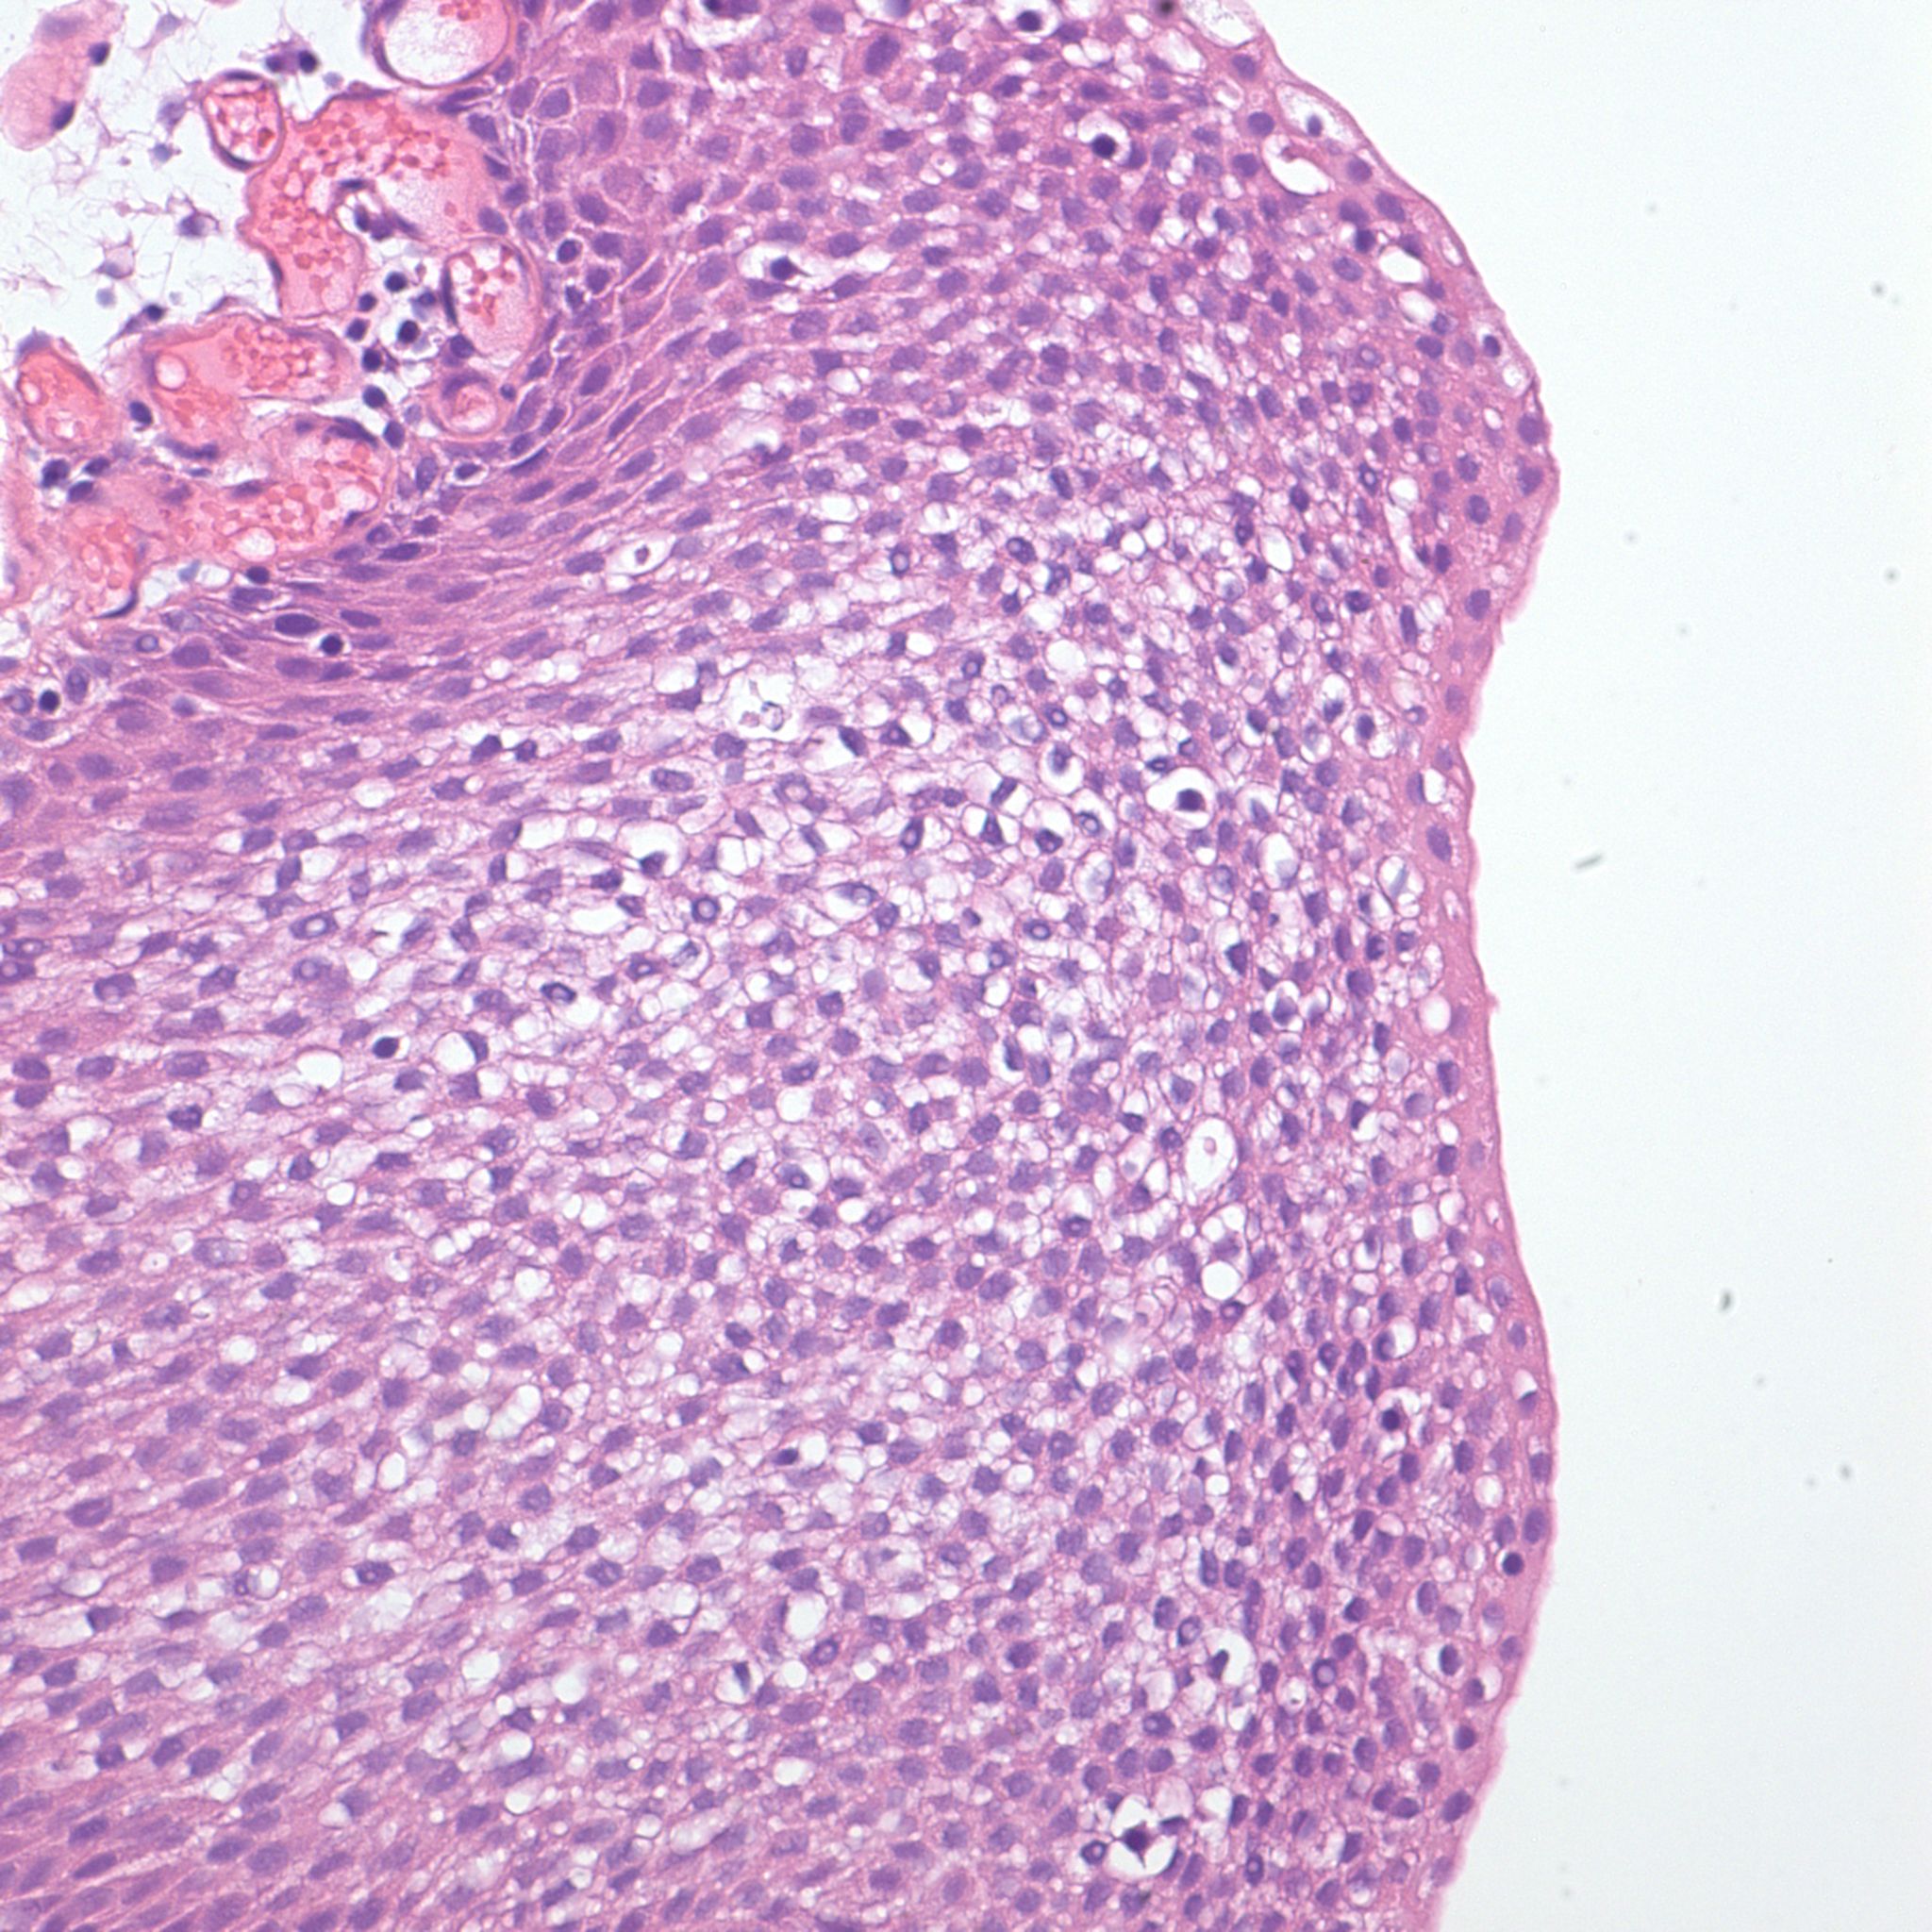

Bladder Papillary Lesions

Case ID: 315